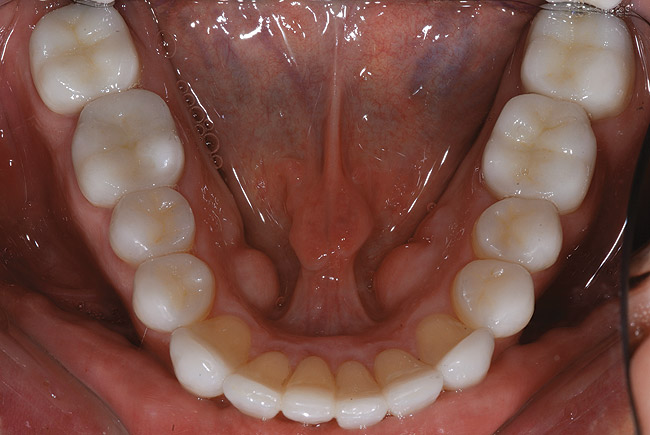

Spre deosebire de amprentele tradiţionale din polivinil-siloxan (PVS) în care toţi dinţii restauraţi trebuie retractaţi şi izolaţi în acelaşi timp, aparatul de scanare orală permite capturarea, la nevoie, a secţiunilor. După finalizarea amprentării digitale, în câteva zile modelele SLA răşinoase se recepţionează de laborator, se aplică pinuri, se secţionează şi sunt pregătite de montare şi fabricarea restaurărilor restante (fig. 7).

Molarii au fost prevăzuţi cu restaurări provizorii utilizând aceeaşi tehnică descrisă anterior. La returnare, coroanele finale au fost probate pentru verificarea contactelor proximale; adaptarea a fost minimă pentru că modelele răşinice SLA sunt extrem de exacte şi durabile.

Fotografiile finale ale acestui caz au pus în evidenţă genul de rezultate care se pot obţine urmând sistemele şi tehnicile dovedite (fig. 8-11). S-au realizat obiectivele de îmbunătăţire a raportului “alb-roz” alături de cele legate de zâmbetul pacientului. Perceperea în mod clar a obiectivelor acestui caz şi capacitatea de a comunica cu acurateţe cu pacientul şi ceramistul reprezintă o parte din cheia succesului.